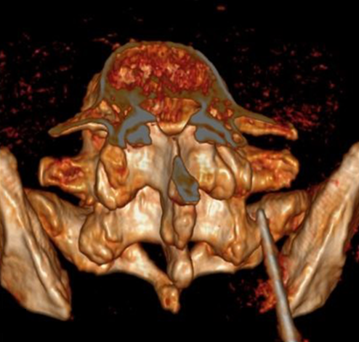

Tali strutture, che si trovano nella pozione posteriore di ciascuna vertebra, hanno una parte attiva nel movimento della colonna vertebrale.

Quando dolore lombare o degli arti inferiori origina da una degenerazione delle faccette articolari, si parla di sindrome delle faccette articolari lombari (sindrome faccettale lombare, lumbar facet joint syndrome).

Come si può notare dalle figure sottostanti, il dolore che origina da patologia delle faccette articolari lombari può irradiarsi in una zona del tutto simile al dolore che si origina dal disco intervertebrale (protrusione o ernia del disco).

La conferma diagnostica arriva dalla indispensabile risonanza magnetica: si va dai reperti di sinovite fino ai più avanzati stadi di osteartrite di più faccette.